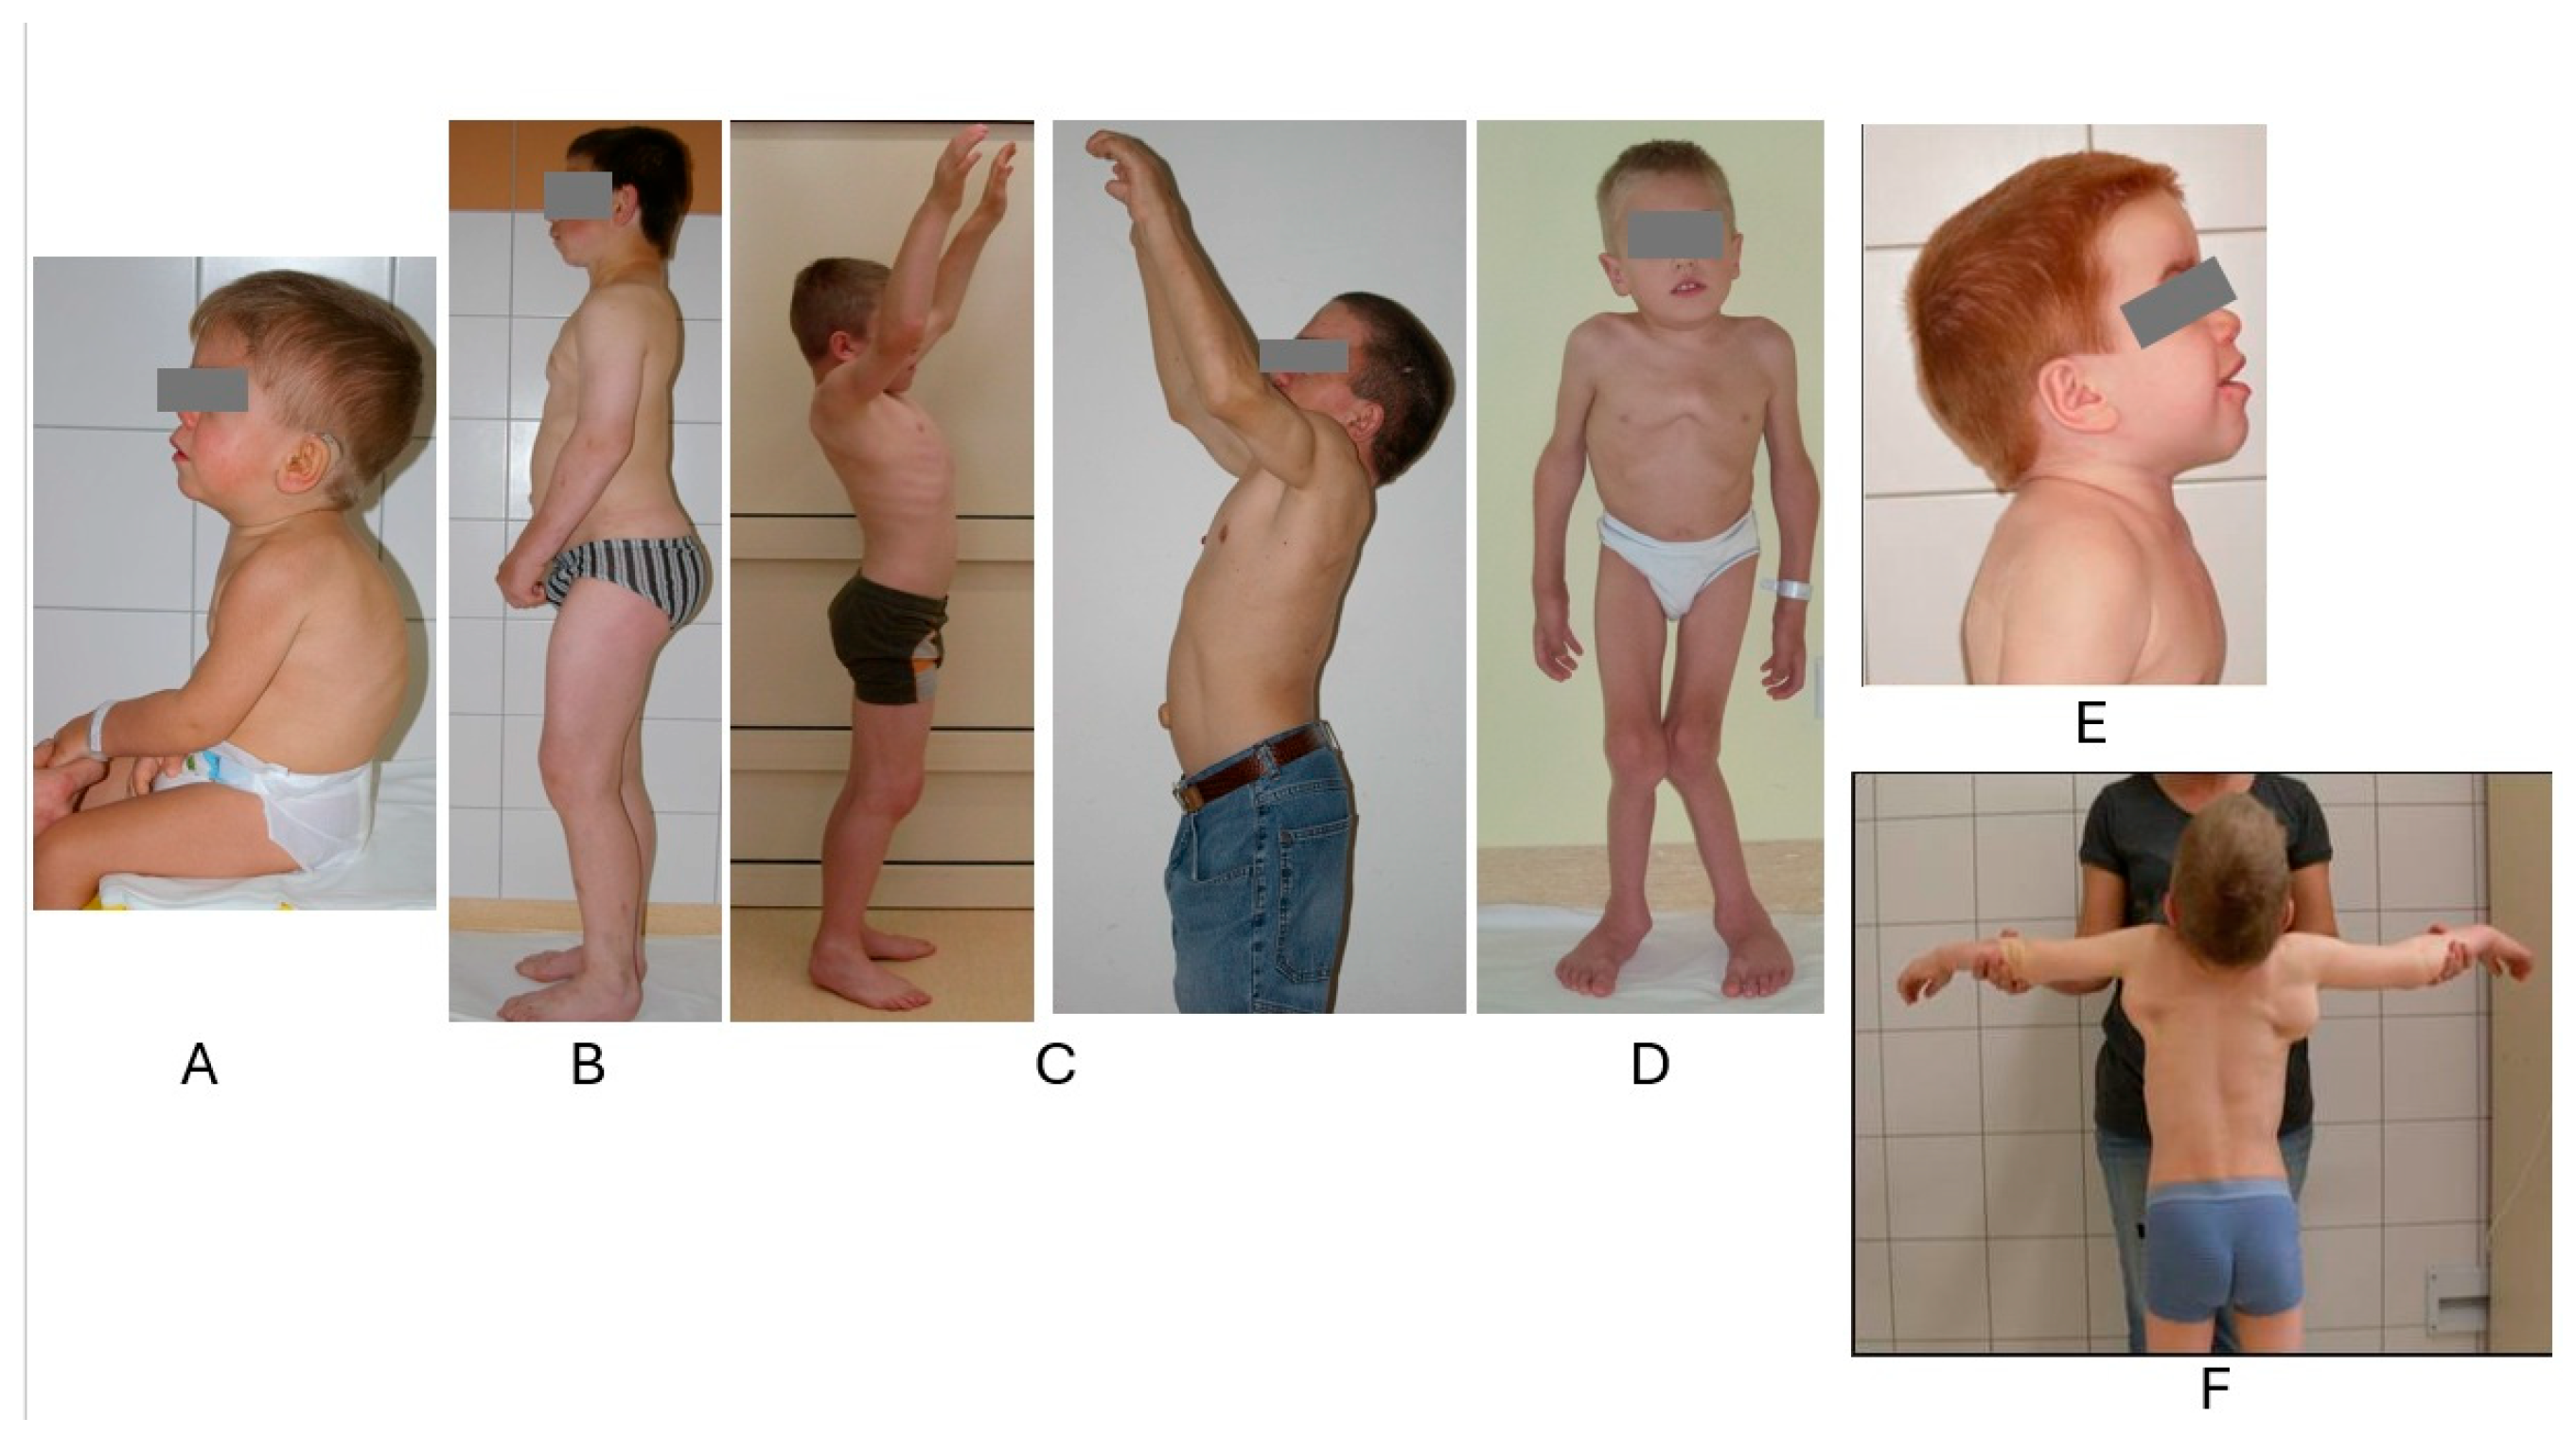

2. Biochemical, Molecular, and Cellular Disorders in MPSs

3. Clinical Manifestation of MPSs

3.1. Main Clinical Symptoms Regarding Accumulated GAGs

3.2. Growth Dynamics

3.3. Skeletal Features